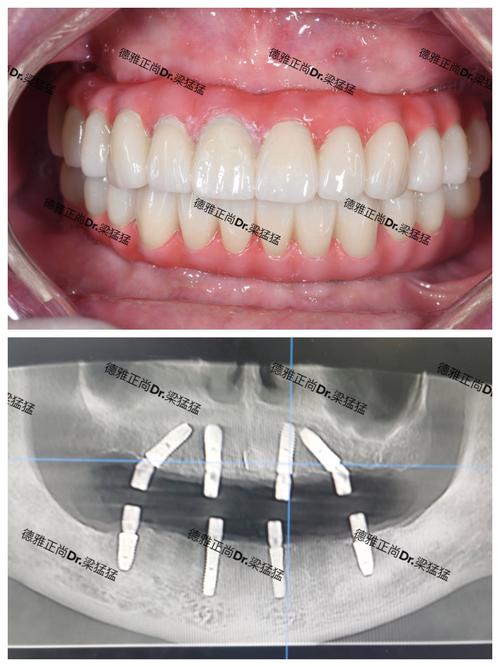

- 要求看案例: 要求查看与你情况(如骨量、缺牙位置、年龄等)相似的真实案例照片和X光片(最好能看到术前术后对比)。

- 深挖医生背景: 重点了解给你做方案和手术的医生,要求查看其资质证明,并当面沟通,感受其专业度和沟通是否顺畅,你完全可以要求更换医生,如果对当前医生不满意的话。